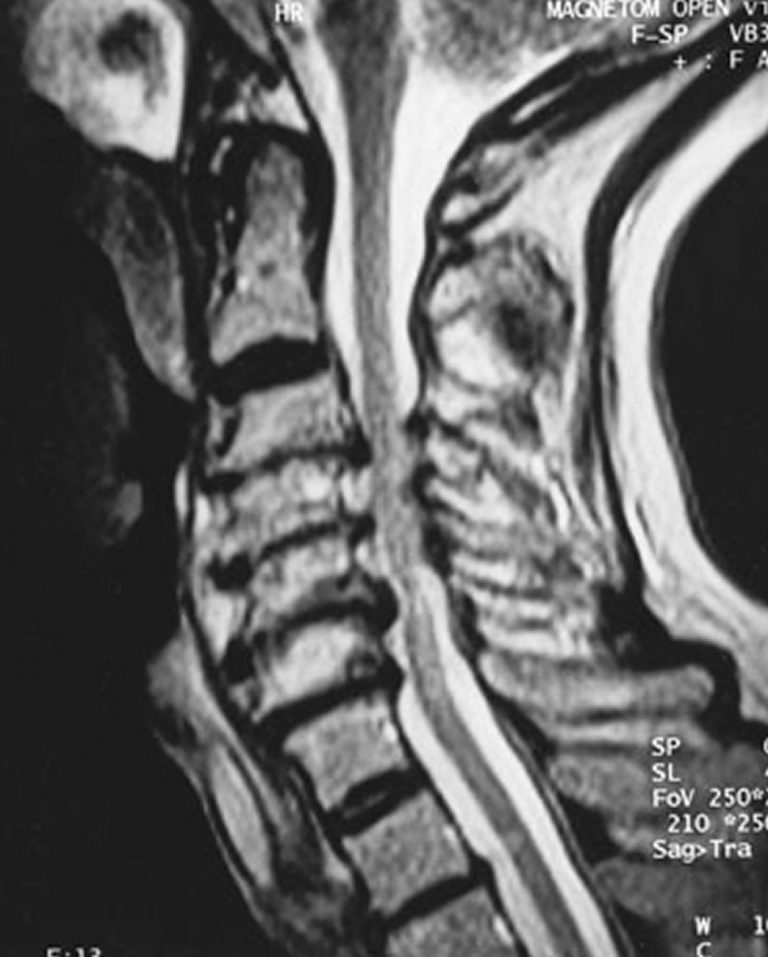

Spinal cord compression of C34, C45, and C56. Download Scientific Spinal Cord Compression Usmle direction of herniation (e.g., posterolateral vs. spinal cord compression can occur from a wide range of underlying conditions. cervical myelopathy is a common form of neurologic impairment caused by compression of the cervical. Far lateral) and the location of the herniation within the spine (e.g., lumbar vs. treatment of potential spinal cord injuries begins at the. Spinal Cord Compression Usmle.